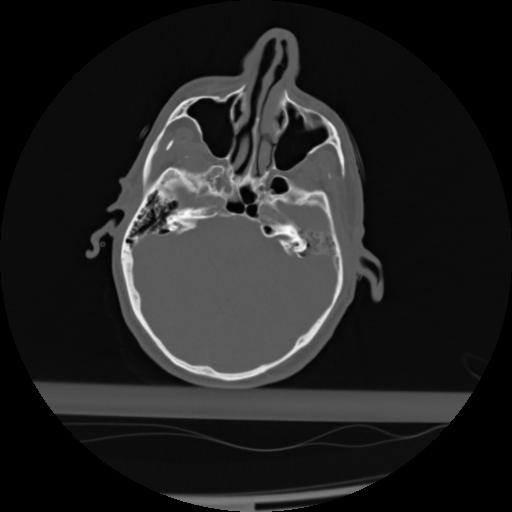

21 ANGIO,CE,Axial,3.0,ANGIO,,